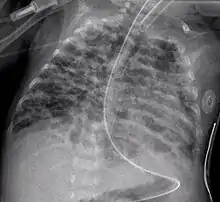

По У.Норсвей и соавт. (1967), различают 4 стадии формирования БЛД, согласно результатам патологоанатомических исследований: первая стадия (1—3-й дни жизни) — выраженный альвеолярный и интерстици- альный отек с гиалиновыми мембранами, ателектазами и некрозами эндотелия бронхиол; вторая стадия (4—10-й дни жизни) — ателектазы становятся более распро- страненными и чередуются с участками эмфиземы, распространяются участки не- крозов и репарации эпителия бронхиол, некротические массы заполняют воздухоносные пути, а на рентгенограмме грудной клетки — «воздушная бронхограмма», легочные поля местами затемнены, но очевидны и участки интерстициальнои эм- физемы; третья стадия (11—ЗО-й дни жизни) — распространенная метаплазия и гипер- плазия эпителия бронхов и бронхиол, участки эмфиземы, окруженные зонами ате- лектаза, массивный интерстициальный фиброз и отек с истончением базальных мембран, альвеол, на рентгенограмме — участки воспаления, зоны ателектазов и появление кист; четвертая стадия (второй месяц жизни) — массивный фиброз легких с деструк- цией альвеол и стенок воздухоносных путей (с метаплазией эпителия), гипертро- фия мышечного слоя бронхиол, уменьшение количества легочных артериол и ка- пилляров с гипертрофией мышечного слоя артериол и венул, рентгенологичес- ки — массивный фиброз легких с отеком и зонами воспаления, уплотнений. Итак, морфологической основой БЛД является развитие интерстициального и внутриальвеолярного фиброза на фоне незрелых анатомических структур лег- ких. Участки интерстициального фиброза выявляют на секции у детей, умерших от СДР, сочетающегося с ВЖКIII—IV степени, уже в конце первой — начале второй недели жизни (Дементьева Г.М. и др., 2000; Попов С.Д., 2002). В дальнейшем фи- брозные изменения в легких становятся более распространенными, при гистоло- гическом исследовании (у умерших от СДР) обнаруживают обширные поля ате- лектазов, дегенеративные изменения в альвеолоцитах и эпителии бронхов, гипер- плазию и метаплазию эпителия бронхов в многослойный плоский в сочетании с мелкими участками эмфиземы. Межальвеолярные перегородки утолщены, отеч- ны; наблюдается пролиферация фибробластных элементов в интерстиции с ги- перпродукцией волокнистых структур. В некоторых участках легких отмечается полная облитерация просвета респираторного отдела легких (бронхиол, альвео- лярных ходов, альвеол). Нередко на секции выявляют и гиалиновые мембраны. В патогенезе указанных поражений решающее значение отводят: • незрелости легочной ткани; • чрезмерному образованию перекисных соединений; • недостаточной активности системы антиоксидантной защиты, что и способ- ствует деструктивным процессам в легких; • отек легких в первые дни жизни способствует этим процессам. На ЭКГ и ЭхоКГ по мере прогрессирования БЛД закономерно отмечают ги- пертрофию правого желудочка, повышение резистентности легочных сосудов, а затем и гипертрофию левого желудочка. Таким образом, БЛД— хронический воспалительный процесс в легких смешанно- го генеза. Маркеры хронической воспалительной реакции при БЛД. В бронхоальвеолярном лаваже у детей с БЛД находят повышенное содержание нейтрофилов с увеличен- ной продолжительностью жизни, повышенную активность эластазы, фибронек- тина, а также такие медиаторы воспаления, как лейкотриены, фактор активации тромбоцитов. В суточной моче этих детей в первую неделю жизни увеличено вы- деление десмозина, указывающее на повышенную деградацию эластазы легких. Повышение продукции эластазы, разрушающей эластин альвеолярной стенки, может привести к нарушению формирования и роста легкого, гиперреактивности бронхов и легочных сосудов. Повышенная концентрация провоспалительныхцитокинов (IL1, IL6, IL8, TNFa) вносит свой вклад в характерную для детей с БЛД бронхоконстрикцию и вазоконстрикцию артериол легких, повышенную проница- емость альвеолярно-капилярных стенок. Решающую роль в формировании и поддержании хронического воспалитель- ного процесса в легких при БЛД, на наш взгляд, играют активированные материн- ские лимфоциты, попавшие к ребенку и обусловливающие на фоне своеобразного гормонального фона клеточную гиперплазию соединительной ткани его легких. БЛД — вариант хронической обструктивной болезни легких (ХОБЛ). Обструк- тивный синдром у детей с БЛД может быть обусловлен как стойкими морфологи- ческими изменениями стенки дыхательных путей, гиперплазией мышечного слоя стенки бронхиол, обструктивным бронхиолитом, так и быть функциональным, связанным с гиперреактивностью — бронхоспазмом на холодный воздух, физиче- скую нагрузку, инфекцию, а возможно, и на аэрозольные антигены. У разных больных БЛД удельный вес упомянутых компонентов в генезе обструктивного синдрома, конечно, различен.

Начальные стадии БЛД характеризуются тем, что обычно у недоношенного ребенка при проведении ИВЛ по поводу СДР не удается через неделю «уйти» от жестких параметров ИВЛ, «зависимости» от высоких величин FiO2- При попытке уменьшить инспираторное давление (PIP) или снизить концентрацию кислорода во вдыхаемой кислородно-воздушной смеси (Fio2 ) развивается дыхательная недостаточность с гипоксемией и гиперкапнией. Необходимость высокого PIP обусловлена повреждением и деструкцией воздухоносных путей, уменьшением легочной растяжимости из-за фиброза и потери эластических волокон. Зависимость от высокого Fio2 связана с гибелью, снижением количества легочных капилляров и артериол, нарушениями капиллярно-альвеолярного обмена газов при фиброзе интерстиция, отеке легочной ткани. Грудная клетка у ребенка приобретает бочкообразную форму, вздута, увеличен ее переднезадний размер (при СДР I типа она имеет вид «спичечного коробка»), имеется втяжение межреберий при дыхании. Отмечается одышка с затруднением выдоха, хрипами на выдохе; может быть и стридор. Однако для детей с БЛД типич- ны и приступы апноэ с брадикардией. Кожные покровы обычно бледные с циано- тичным оттенком. Показатели Ро2 в крови у этих детей в первом полугодии жизни остаются сниженными, нередко достигая 45—50 торр (мм рт.ст.). Обращает на себя внимание стойкость рентгенологической картины легких в виде чередования участков пониженной прозрачности легочной ткани, чаще среднемедиальных от- делов, грубого интерстициального рисунка (фиброза) и участков гипервоздушно- сти. У многих детей периодически повторяются долевые или сегментарные ате- лектазы, а у части детей с тяжелой БЛД развивается трахеобронхомаляция. При изучении функционального состояния легких выявляют: повышение часто- ты дыхания, уменьшение дыхательного объема (при относительно нормальной минутной легочной вентиляции), низкий динамический легочный комплайнс (растяжимость легких), увеличение остаточного объема, признаки повышения ре- зистентности в бронхиолах, высокое Расог крови, подъем артериоальвеолярной разницы Расо2 , гипоксемию. Все это приводит к увеличению работы дыхания и требует повышения калорийности пищи. Очень часты у детей с БЛД приобретенные инфекционные процессы в легких, пневмонии, вызванные не только бактериями, но и грибами. У них всегда тяжело протекают респираторные вирусные инфекции и особенно тяжело вызванные ре- спираторно-синцитиальным вирусом. Персистирующая легочная гипертензия — характернейшее проявление БЛД; она может приводить к правожелудочковой недостаточности, развитию легочного сердца с кардиомегалией, гепатомегалией и задержкой жидкости. Обычно дети с БДД склонны к срыгиваниям, рвоте, аспирации пищевых масс, недостаточно прибавляют в массе, у них развивается гипотрофия типа гипостату- ры. У всех детей с БЛД на первом году жизни отмечаются повторные приступы бронхообструктивного синдрома, высока частота анемий, рахита, а приблизительно у 15% детей в возрасте 3—4 лет проявляются приступы бронхиальной астмы (Де- ментьева Г.М. и др., 2000).

Диагноз. Общепринятых критериев ранней диагностики БЛД нет. Предложены следующие четыре критерия для диагностики БЛД: • необходимость ИВЛ по крайне мере в течение 6 дней (по нашему мнению, в течение трех дней) на первой неделе жизни (обычно с положительным дав- лением на выдохе и длительным высоким F102); • Рао2 в крови 50 торр (мм рт.ст.) и менее, и для подъема его необходима кис- лородотерапия до возраста более 28 сут. (по Jobe А.Н. и Bancalari E.H., 2001, до 36 нед. гестационного возраста); • хронический респираторный дистресс (одышка, ретракция грудной клетки, дыхательные шумы, выявляемые при аускультации или слышимые на рас- стоянии) и наличие признаков явной дыхательной недостаточности и при- знаков периодического бронхообструктивного синдрома, продолжающихся не менее 28 суток; • торпидные рентгенологические изменения — в легочных полях плотные оча- ги (зоны фиброза) чередуются с зонами повышенной прозрачности, т.е. ги- перинфляции («пчелиные соты»), диафрагма опущена, межреберные проме- жутки расширены, тень сердца увеличена в размерах, контуры сердца неот- четливые, размытые. Согласно A.H.Jobe и Е.Н.Bancalari (2001), выделяют три степени тяжести БЛД: Легкая — потребность в кислородной поддержке до 28-го дня жизни и старше, но ее прекращение до 36 нед. гестационного возраста. Средней тяжести ~ потребность в кислородной поддержке до 28-го дня жизни и старше, но Fio2 <0,3 в 36 нед. гестационного возраста. Тяжелая — необходимость в кислородной поддержке в 36 нед. гестационного возраста с F1O2 >0,3.